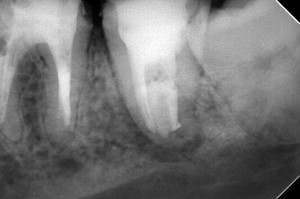

樋状根というのはその名の通り、神経管が癒合して雨どいのようなU字型になる現象の事で、アジア人は樋状根の確立が超高いのです( 一一)

今回紹介したケースは3根尖のC2です。